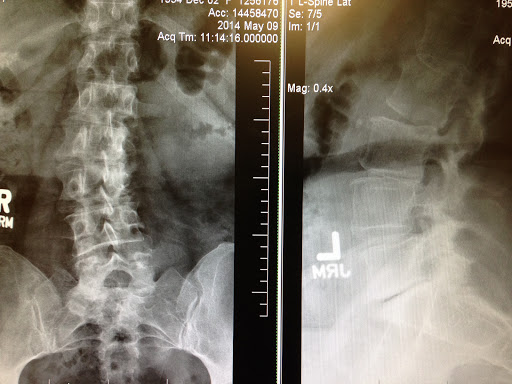

I was in such severe pain when I found Dr. Allen, I really had lost hope in living a full happy life as my pain had become unmanageable. Dr. Allens gentle, confident, holistic, well trained whole body approach in dealing with my severe pain from injured lumbar and neck, saved me from intense daily pain. Through his use of very customized gentle specific maneuvers to realign my scoliotic spine and neck, and with his laser treatments, I now can enjoy life without surgery and movement without debilitating pain. Being pain free is a miracle I can attribute to Dr. Allen. Thank you so much. You are blessed and gifted beyond your education and training!!! Susie Jerome, PsyD.